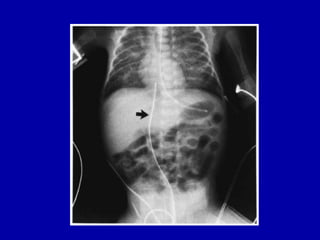

X-ray - MAS

MAS

46